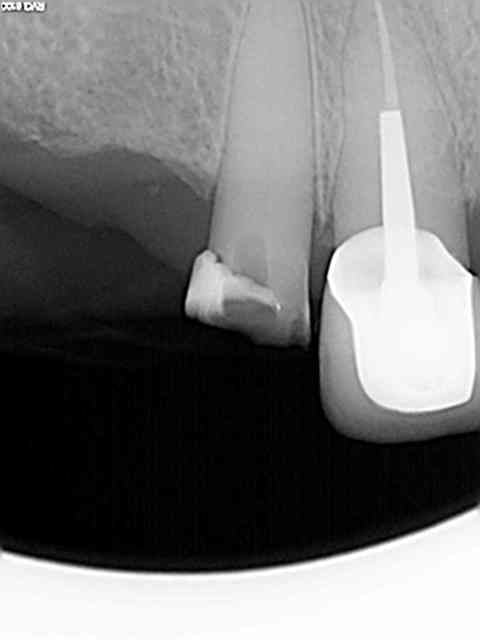

Exemple sur cette 12 tout à l'heure, 1h 30 de rdv terminé en 1h et encore j'ai un peu "tâtonné" pour trouver la pulpe. Toujours pas de cathétérisme manuel of course sinon j'y serais encore.)))))